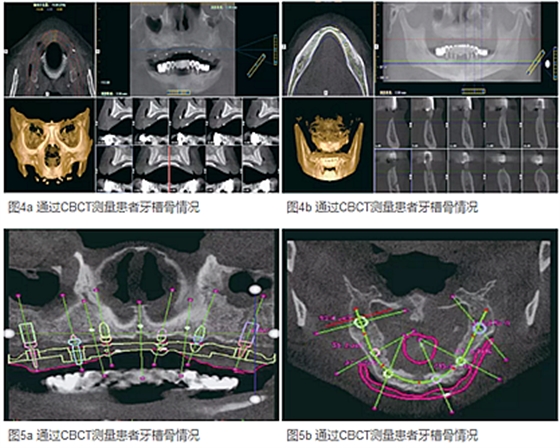

既往體健,有吸煙史(15支/天)。初診檢查發(fā)現(xiàn)原有活動義齒固位較差,口唇豐滿度欠佳,面容蒼老,下頜為雙側尖牙、第一前磨牙、第二前磨牙支持式的整體橋固定修復,口內(nèi)檢查發(fā)現(xiàn)下頜基牙全部松動,尖牙周圍牙齦紅腫、溢膿,余留天然牙無保留價值。CBCT顯示上頜牙槽骨吸收不均勻,上頜右側尖牙、左側側切牙、雙側第二前磨牙和第二磨牙區(qū)骨量尚可,滿足種植固定修復要求;下頜牙槽骨條件較好,滿足種植固定修復要求。

(1)通過檢查發(fā)現(xiàn)原有義齒咬合關系和垂直高度尚可,利用原有義齒制作放射性診斷導板,讓患者戴入原有義齒拍攝CBCT,同時對原有義齒單獨拍攝CBCT。將2組CT數(shù)據(jù)傳輸?shù)綌?shù)字化導板加工中心進行整合,生成帶有義齒信息的種植體外科規(guī)劃軟件。

(2)在規(guī)劃軟件中根據(jù)CBCT測量結果,結合義齒修復信息,實現(xiàn)以修復為導向的種植體設計。計劃上頜在右側尖牙、左側側切牙、雙側第二前磨牙位點、雙側第二磨牙位點植入6顆種植體。下頜在雙側側切牙和尖牙之間、雙側第一前磨牙和第二前磨牙之間、雙側第一磨牙位點植入6顆種植體。